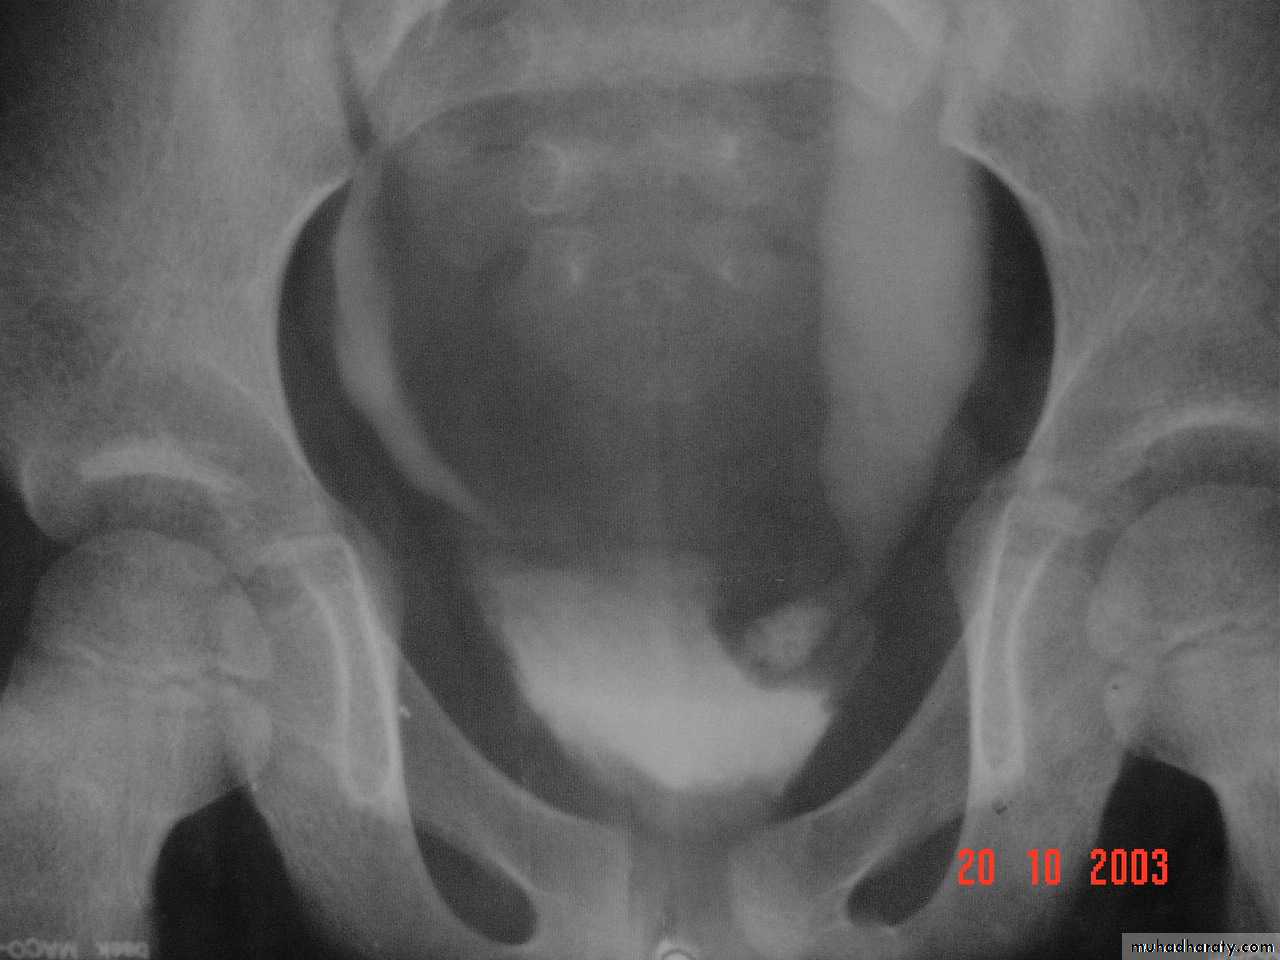

The middle third of right ureter curve medially behind the IVC , then laterally to regain it’s normal position , this lead to obstruction of upper third of ureter.Ureterocele :

Congenital cystic dilatation of lower end of ureter ( intra-mural part) due to pin-hole meatus . May be simple or ectopic .simple : the orifice is in proper position of bladder ,

Ectopic >> in bladder neck , urethra , uterus & vagina .

IVU :

- There is rounded or elliptical dilatation of lower end of ureter with thin lineal filling defect around it , resembling (cobra head appearance),

- Proximal dilatation of rest of ureter .

- In advanced cases hydronephrosis .

- In obstructed ureterocele , filling defect in the bladder

Ectopia vesica :

bladder located at low position & plain x-ray shows separation of symphysis pubis .